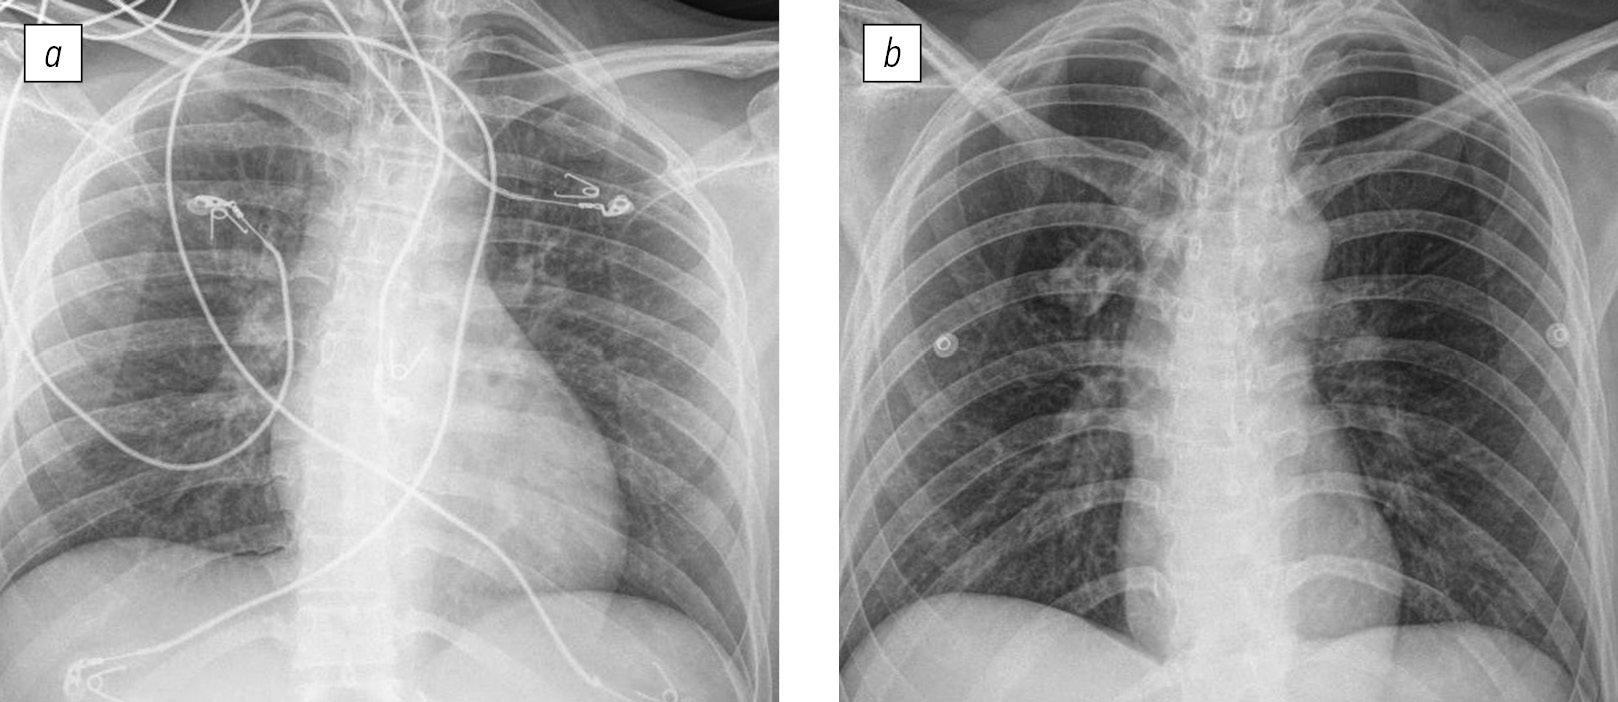

Рис. 2. Рентгенограммы органов грудной клетки в прямой проекции пациента В (39 лет, рассчитанная начальная концентрация карбоксигемоглобина в крови 15%, легкая степень интоксикации), выполненные на 1-е (а) и 4-е (b) сутки после поступления.

Fig. 2. X-rays of the chest organs in the direct projection of patient B (39 years old, calculated initial concentration of carboxyhemoglobin in the blood is 15%, corresponds to a mild degree of intoxication), performed on days 1 (а) and 4 (b) after admission.

Длительность госпитализации пациентов с интоксикацией тяжелой степени составила 4 [4; 6] сут, средней степени — 4 [2; 5, 7] сут, легкой степени — 3 [2; 5, 5] сут. Значимых различий по длительности госпитализации пациентов в зависимости от степени тяжести состояния, определенного по рассчитанной начальной концентрации карбоксигемоглобина в крови, выявлено не было. Доля пациентов, у которых выявили интерстициальные изменения в легких, значимо не зависела от степени тяжести состояния (табл. 1). Так, у пациентов с тяжелой (рис. 1) и легкой (рис. 2) степенью состояния определены сходные интерстициальные изменения в тканях легких на рентгенограммах органов грудной клетки. В то же время у 37 ± 15% пациентов в тяжелом состоянии интерстициальных изменений в тканях легких при анализе рентгенограмм органов грудной клетки выявлено не было (рис. 3).

У 47 ± 7% пациентов были выявлены интерстициальные изменения в тканях легких: усиление легочного рисунка за счет сосудистого компонента, очаги консолидации легочной ткани. При анализе рентгенограмм таких пациентов в динамике отметили нормализацию легочного рисунка и регресс очагов консолидации (рис. 1, 2). Длительность госпитализации пациентов с выявленными изменениями на рентгенограммах составила 5 [4; 8] сут, без интерстициальных изменений (53 ± 7%) — 3 [2; 5] сут.